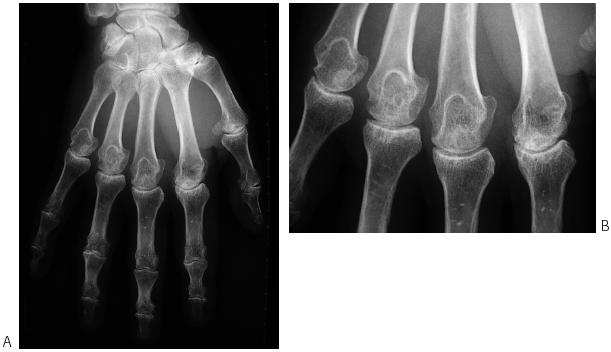

– des signes d’arthropathie chondrale et sous-chondrale sur des articulations peu touchées par l’arthrose, notamment les deuxièmes et troisièmes métacarpophalangiennes, avec des géodes cernées par une condensation et disposées dans la zone osseuse sous-chondrale, des ostéophytes à extrémité arrondie ou acuminée en hameçon (figure 33.1)

– arthropathies chroniques, de type le plus souvent mécanique, mais parfois de type inflammatoire. L’atteinte peut être mono-, oligo- ou polyarticulaires, de gravité variable, depuis de simples arthralgies jusqu’à des troubles articulaires sévères et invalidants. Elle concerne plus particulièrement les articulations métacarpophalangiennes, notamment les deuxièmes et troisièmes, mais elle peut s’étendre aux interphalangiennes proximales et aux poignets, voire aux grosses articulations des membres supérieurs et inférieurs. En général, n’existent au début que des douleurs ou une limitation de la flexion, puis peut survenir une tuméfaction chronique, voire une déformation, en général non ou peu inflammatoire;